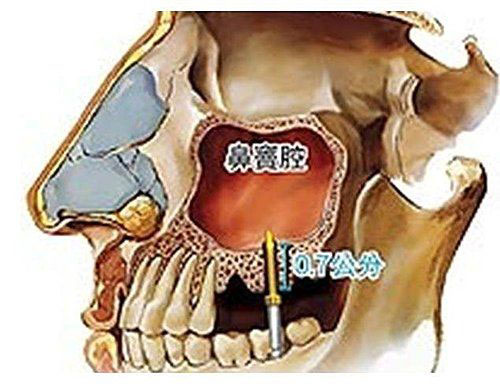

口腔上顎後牙區僅有薄薄一層上顎骨與鼻竇腔相隔,若要在此部位進行植牙手術重建咬合功能, 必須先進行鼻竇增高術,以期植體獲得最佳穩定度。 |

不同的牙齒有不同的牙根型態,惟有足夠的骨質與骨量,才有最穩定的人工植牙。 |